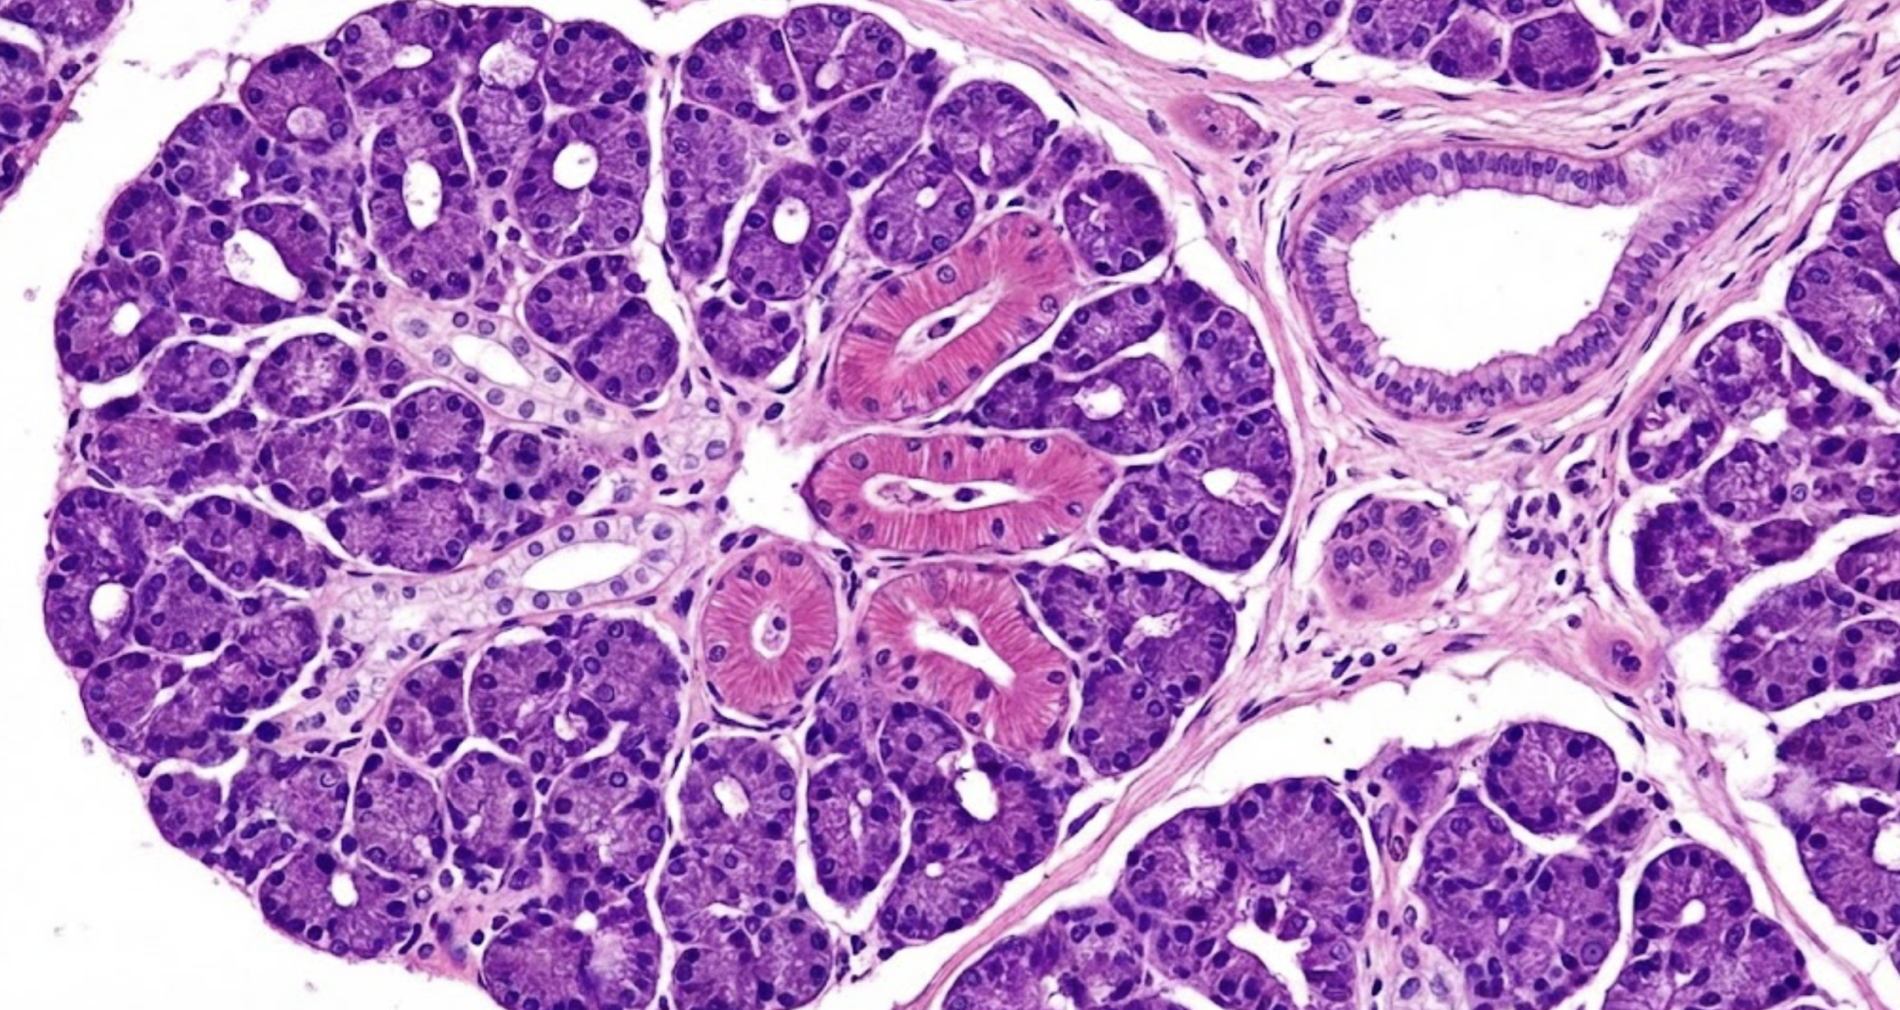

2.34 Das abgebildete Präparat zeigt einen typischen Querschnitt durch das Gewebe eines Organs. Um welche der folgenden Drüsen handelt es sich?

- (A) Glandula thyroidea

- (B) Glandula parotidea

- (C) Glandulae suprarenales

- (D) Glandula pancreatica

- (E) Glandula pituitaria